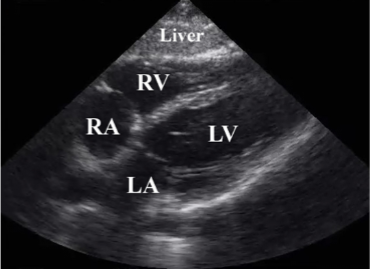

What ultrasound image is shown?

Subxiphoid